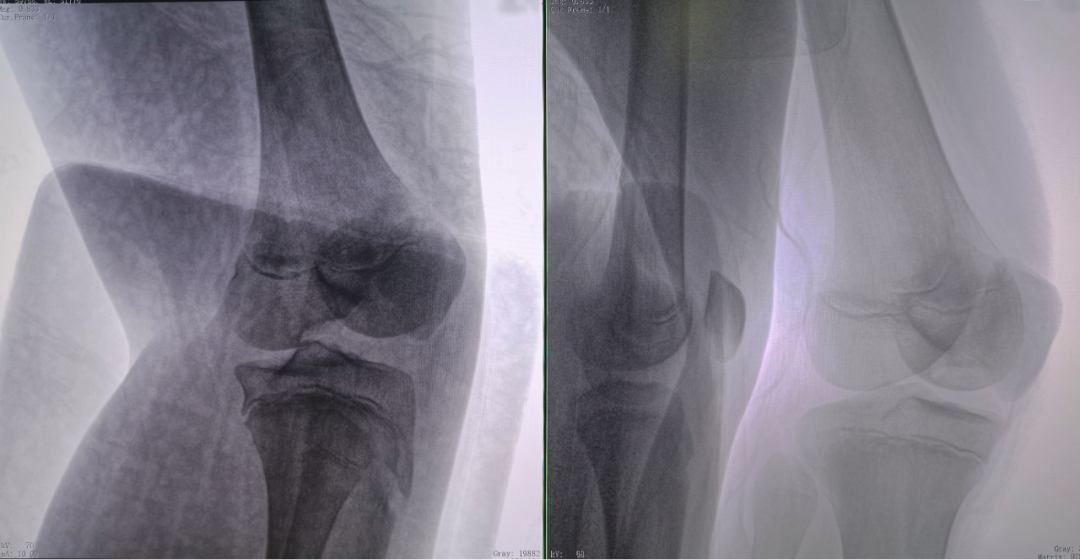

二維C形臂提供的影像存在固有局限性,其成像原理是基于單一方位的投影,導致深部解剖結構信息缺失,且容易受到骨骼和組織的重疊干擾,使得部分病灶難以清晰顯示,甚至被掩蓋。相比之下,三維C形臂通過三維重建技術,可以獲得類似CT的斷層掃描圖像,從而解決了二維影像的重疊問題。

醫生能夠利用這些三維圖像,更直觀、更深入地分析病變,進行全方位觀察,例如:精確評估骨折復位情況、清晰顯示內植入物的位置及其與周圍組織的關系等。尤其在復雜骨折、脊柱手術、呼吸介入等臨床場景中,三維C形臂提供的詳細信息對手術導航和療效評估至關重要。